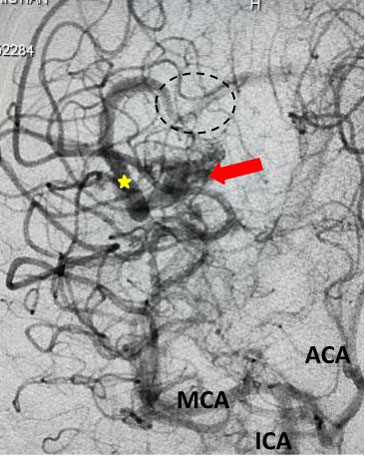

Fig 1. Head CT scan showing large right-sided, parieto-occipital intra-cerebral hemorrhage (ICH) and small occipital and temporal subdural hemorrhage (SDH) with right to left midline shift (red arrow).

A head CT revealed a large posterior-parietal intracerebral bleed, an acute subdural clot, and right to left midline shift (Fig 1). Following the review of a head CTA, the patient was diagnosed with a ruptured brain arteriovenous malformation (AVM). Urgent treatment was indicated for this acute intracerebral hemorrhage (ICH) with significant mass effect and the risk of catastrophic rebleeding of the AVM.